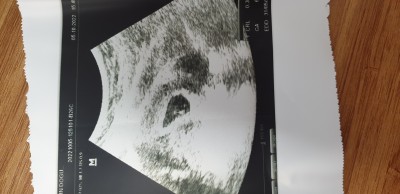

Arkadaşlar dr ikiz demedi ama herkes ikiz diyor sizde yorum yapar mısınız

image

Gebelik haftası 8 haftalık

Iki kese de doluymuş güya

Ben tek kese görüyorum, nasıl ikiz diyorlar anlamadım

Canım benim ikiz ama 6 haftada 2 kese var dedi ikiz olsa doktor neden soylemesin

İki kese gibi görünüyor kağıt ama olsaydı söylerdi doktor belki ultrason çekilirken böyle gölgeli çekilmiştir bilemedim bende iki kese gördüm sanki:D